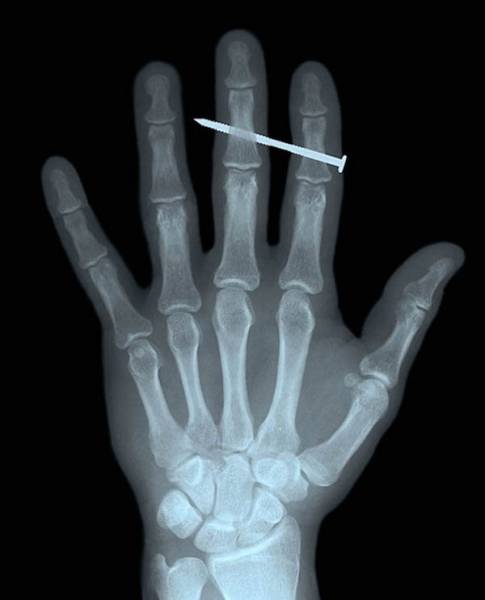

#16 Naula sormen läpi